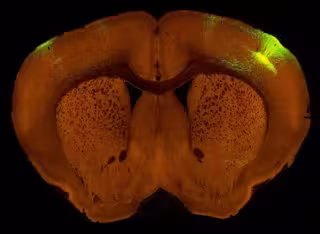

Sección del cerebro de un ratón.

Sección del cerebro de un ratón. - ALLEN INSTITUTE

Para obtener una visión más detallada de cómo está conectado el cerebro de los mamíferos, los investigadores estudiaron las conexiones entre clases específicas de neuronas que cubren dos partes principales del cerebro, la corteza y el tálamo. Los experimentos del equipo se basaron en un virus especialmente modificado que rastrea las rutas de las neuronas, iluminando las rutas de información del cerebro en colores brillantes.

El conjunto de datos recién adquirido captura las conexiones entre las neuronas en el tálamo y la corteza, utilizando etiquetas especiales para iluminar cinco tipos diferentes de neuronas que habitan en diferentes capas de la corteza.